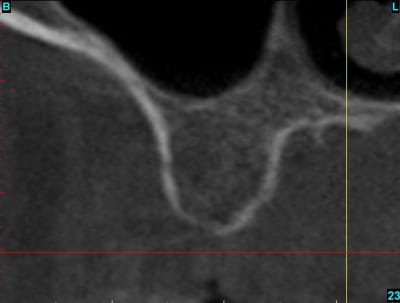

Si si! , il y a bien une image sur chacune des deux coupes.

ps: c'est vrai que après coup, on voit une densité différente sur les coupes avec une limite circulaire...

on voit toujours mieux à la radio ce que l'on a trouvé en clinique ...

je ne l'aurai pas vu avant après en ouvrant très très grand les yeux on trouve !

sinon, j'avoue en toute honneteté n'avoir rien détecté lors de l'étude du scanner. aprés coup, c'est vrai que quand on sait ce qu'on doit chercher, on discerne...vaguement...